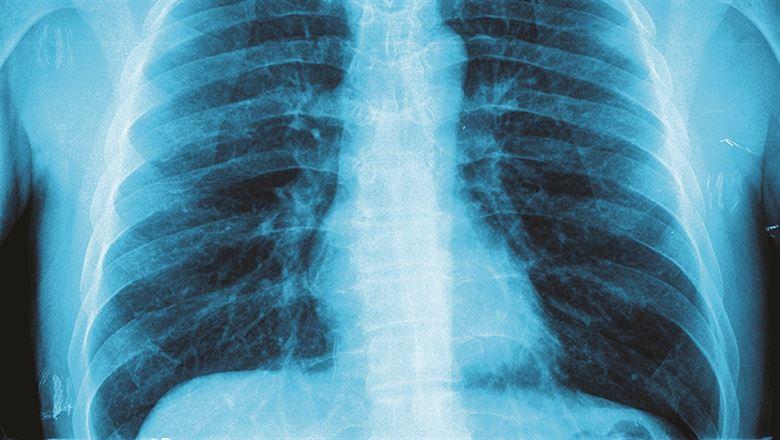

chest x-ray Associations Now January/February 2017 Issue By: Alex Beall

In a country with high risk of lung disease and related conditions, the American College of Chest Physicians' fellowship programs trains Chinese lung doctors in patient care.